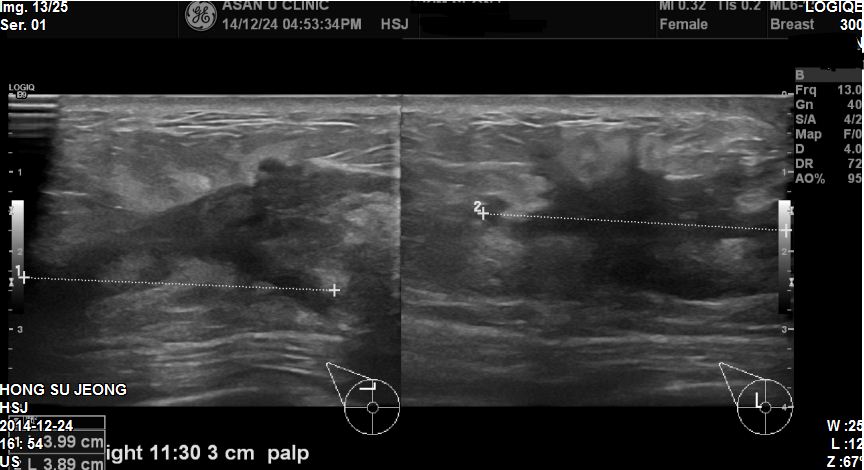

1주전부터 우측유방에 만져지는 혹이생겨 본원내원하신 39세 여자환자분이십니다

본원초음파상 11 : 30 방향에 3.9cm 혹과 겨드랑이에 림프절이 많이 부어있어

유방조직검사와 겨드랑이 세포검사시행하였고 결과

침윤성유방암이 진단되었고 겨드랑이까지 전이가 되어있었습니다.